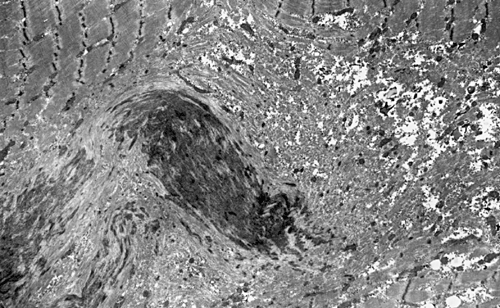

On hematoxylin-eosin stained sections, there is an increased variation of fiber diameter with many atrophic fibers intermingled with fibers of normal caliber. There is no evidence of fiber grouping or perifascicular atrophy. No inflammatory cells are present. There is also mild interstitial fibrosis (Panel A). On higher magnification, many fibers have a round concentric structure (Panel B). Irregular, centrally located depositions are also identified on modified Gomori's trichrome. The concentric nature, however, is not as obvious as in the hematoxin-eosin stained sections (Panel C). Type I and II fibers are not clearly separated in the ATPase preparation at pH 9.4. This is a common situation in chronically ill muscle (Panel D). The type I fibers are unusually dark. There is an increase in the proportion of type I fibers. The atrophic fibers are usually type II fibers. The concentric lesions are found predominantly in type I fibers (Panel E). There is an increase in PAS staining which is consistent with increased glycogen storage (Panel F). No increase in lipid content is demonstrated by oil red O (Panel G). On NADH-TR reaction, the concentric structures appear to have a clear central core that is devoid of enzymatic activity, a rim with intense enzymatic activity and a surround zone with relatively normal reactivity. These features are classic for target fibers (Panel H and I). No deficiency of laminin-2 (merosin) (Panel J) or dystrophin (Panel K) is demonstrated by immunohistochemistry. The central lesions are also immunoreactive for both laminin-2 and dystrophin. Immunohistochemistry for desmin demonstrate a core of strong immunoreactivity and also strong reaction in the sarcoplasmic membrane (Panel L and M). The target structures are also well demonstrated on semithin sections (Panel N). On electron microscopy, z-disc streaming is a common finding and they are often admixed with a substantial amount of dense granular electron dense substance (Panel O and P). There are also numerous cytoplasmic bodies characterized by radiating intermediate filaments (spheroid bodies) (Panel Q and R).